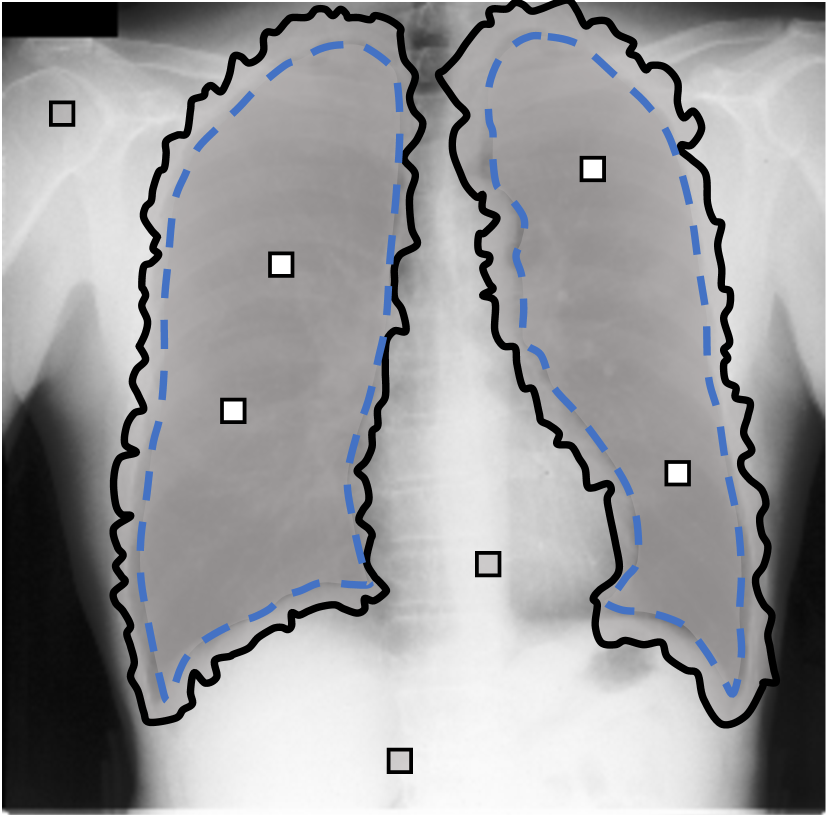

A few existing segmentation label noise approaches (Zhu et al., 2019; Zhang et al., 2020b; a) directly apply methods in classification label noise. However, these methods assume the label noise for each pixel is i.i.d. (independent and identically distributed). This assumption is not realistic in the segmentation context, where annotation is often done by brushes, and error is usually introduced near the boundary of objects. Regions further away from the boundary are less likely to be mislabeled (see Fig. 1(c) for an illustration). Therefore, in segmentation tasks, label noise of pixels has to be spatially correlated. An i.i.d. label noise will result in unrealistic annotations as in Fig. 1(b).

We propose a novel label noise model for segmentation annotations. Our model simulates the real annotation scenario, where an annotator uses a brush to delineate the boundary of an object. The noisy boundary can be considered a random yet continuous distortion of the true boundary. To capture this noise behavior, we propose a Markov process model. At each step of the process, two Bernoulli variables are used to control the expansion/shrinkage decision and the spatial-dependent expansion/shrinkage strength along the boundary. This model ensures the noisy label is a continuous distortion of the ground truth label along the boundary, as shown in Fig. 1(c). Our model also includes a random flipping noise, which allows random (yet sparse) mislabels to appear even at regions far away from the boundary.

For each of these three datasets, we use three noise settings, denoted by , and . and are two settings synthesized by our Markov process with (expansion) and (shrinkage), respectively. Figure 4 shows examples of our synthesized label noise. We also include the mix of random dilation and erosion noise used by previous work (Zhu et al., 2019; Zhang et al., 2020b; a). This is achieved by randomly dilate or erode a mask with a number of pixels. Note that our Markov label noise can theoretically include this type of noise by setting . Detailed parameters for these settings are provided in the Appendix.

Real-world label noise. To evaluate with real-world label noise is challenging. We are not aware of any public medical image segmentation dataset that has both true labels and noisy labels from human annotators. Therefore, we use a multi-annotator dataset, LIDC-IDRI dataset (Armato III et al., 2015; Armato et al., 2011; Clark et al., 2013), and the coarse segmentation in a vision dataset, Cityscapes (Cordts et al., 2016). The LIDC-IDRI dataset consists of 1018 3D thorax CT scans where four radiologists have annotated multiple lung nodules in each scan. The dataset was annotated by 12 radiologists, and it is not possible to match an annotation to an expert. We use the majority voting as the true labels and the union of four annotations as noisy labels. We process and split the data exactly the same way as Kohl et al. (2018). Cityscapes dataset contains 5000 finely annotated images along with a coarse segmentation by human annotators that we use as the “noisy label”. We only focus on the ‘car’ class because (1) cars are popular objects and are frequently included in images; (2) the coarse annotation of cars is very similar to noisy annotation in medical imaging – they are reasonable distortions of the clean label without changing the topology. See Figure 4(c) for an example. The detailed settings of LIDC-IDRI and Cityscapes can be found in Appendix A.2.1.